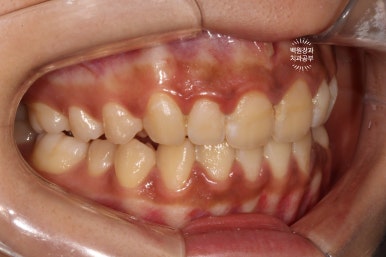

지금 잇몸 상태가 치석제거와 잇몸치료를 모두 완료한 직후입니다.

흡연으로 인한 약간의 잇몸 착색은 있지만, 붉고 부어 있었던 잇몸은 온데간데 없고, 너무나 깨끗한 잇몸상태를 되찾았죠...? 잇몸의 색깔은 선홍색으로 돌아왔고, 날씬하고 얇아진 모습입니다.

위 사진은 충치를 갓 제거하고 나서의 사집입니다.

충치가 넓기도 하였지만, 자연스러운 색조 재현을 위해 널찍하게 치아삭제를 시행하였습니다.

bevel도 길게 주고..

잇몸의 하방에 삽입되어 있는 코드는 충치치료 직후 제거될 예정입니다.

깊이 있는 충치가 잘 보이게 하기 위함이죠.